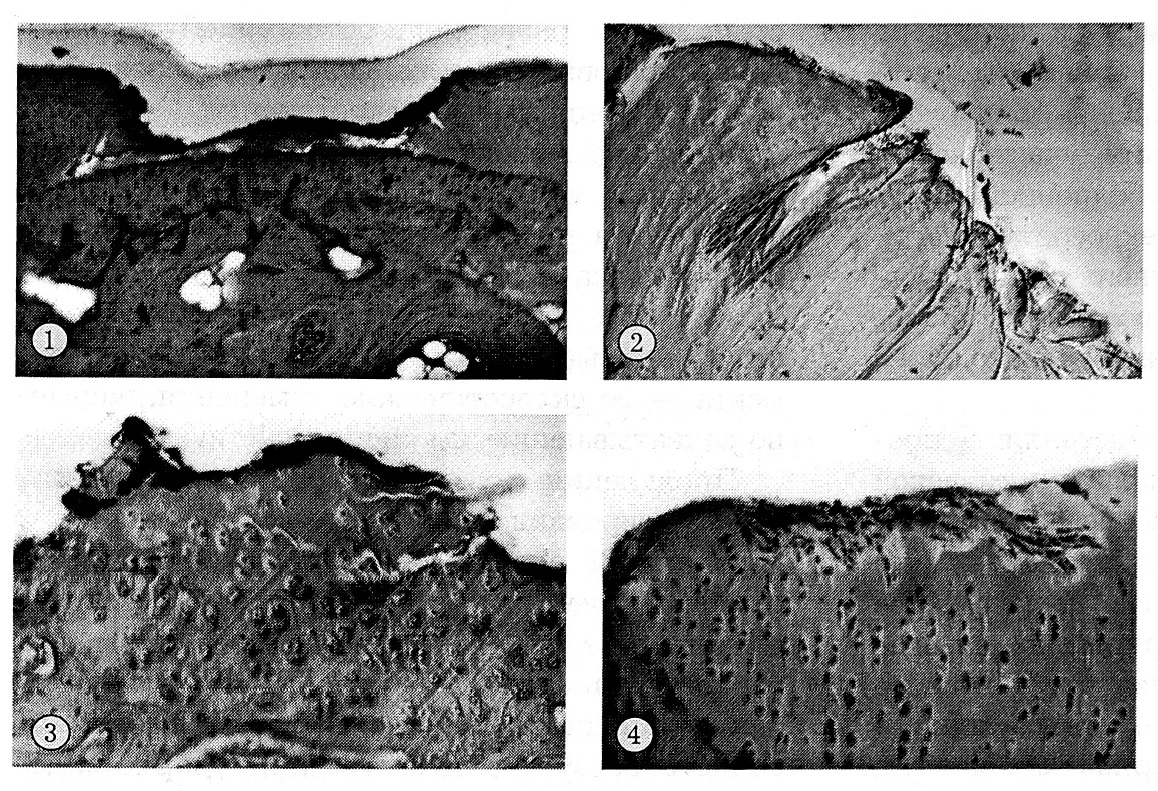

Результаты гистоморфологических исследований свидетельствовали о том, что в условиях проведенного эксперимента в наибольшей степени страдает суставной хрящ головки бедренной кости, подвергающийся непосредственному воздействию повреждающего агента. Картина механической деструкции хряща характеризуется значительным разнообразием формы, глубины и протяженности повреждения. В редких случаях она ограничивается небольшими очагами или более протяженными зонами разрушения свободного края хряща с образованием поверхностных дефектов, иногда проникающих неглубоко в подлежащие участки верхнего слоя. Чаще обнаруживаются узкие или более широкие щелевидные дефекты, которые идут в радиальном, реже в косом направлении, порой до субхондральной костной пластинки. В других случаях происходит частичное отщепление хряща от костной пластинки и даже встречаются участки, где на том или ином протяжении хрящ вообще отсутствует (рис. 1). Иногда при внешне неповрежденном хряще в его слоях, в том числе в глубоком, обнаруживаются звездообразные, порой многолучевые разрывы. Такие деструктивные изменения редко бывают изолированными — чаще им сопутствует более существенное разрушение хряща, в том числе его размозжение с образованием глубоких и широких дефектов в виде бухт и узур с ровными или деформированными краями, занимающих значительную часть толщи или всю толщу хряща, а также широких, чаще неровных и тоже глубоких щелей. При этом часть поврежденного хряща может фрагментироваться и отторгшиеся участки его либо свободно располагаются в просвете дефекта, либо сохраняют слабую связь с его краями в виде перемычек разной ширины и протяженности.

Механическая деструкция хряща вертлужной впадины встречается намного реже, чем головки, и выражена незначительно. Глубокие бухты и узуры практически отсутствуют, щелевидные дефекты представляются более поверхностными и узкими.

Другим важным следствием механической травмы сустава являются некрозы хряща. В гистотопографическом отношении их можно разделить на два основных варианта, которые нередко сочетаются в разном количественном соотношении. В очагах значительной механической деструкции, в основном в головке бедренной кости и в непосредственной близости к очагу разрушения, неизбежно некротизируются отторгающиеся фрагменты хрящевой ткани, свободный край хряща и даже вся толща хрящевого покрова (рис. 2). Полнослойному некрозу часто подвергается хрящ периферических отделов головки в участке сопряжения ее с шейкой бедренной кости. Постоянно наряду с обширными некрозами, а порой и при их отсутствии омертвевают края даже небольших по протяженности и глубине щелевидных дефектов хряща или бухт и узур.

Аналогичные изменения происходили и в вертлужной впадине, однако значительно реже и с существенно меньшими степенью деструкции хряща и кости, инволюции костного мозга, проявлениями остеопороза и гемоциркуляторных расстройств (рис. 3).

Рис. 1. Язвоподобный дефект, доходящий до субхондральной пластинки (3 сут после травмы головки бедренной кости). Ув. 35. 2. Глубокие щелевидные дефекты хряща с его некрозом (9 мес после травмы головки бедренной кости). Ув. 90. 3. Щелевидные дефекты хряща вертлужной впадины; неровный свободный край с участком поверхностного некроза (7 сут после травмы головки бедренной кости). Ув. 90. 4. Замещение поверхностного дефекта хряща головки пролиферирующими соединительнотканными клетками (3 сут после травмы большого вертела). Ув. 90.

Анализ репаративных процессов показал, что мелкоочаговые неглубокие дефекты свободного края суставного хряща и небольшие участки поверхностного некроза уже в первые дни после травмы начинают выстилаться волокнистой соединительной тканью и в конечном итоге замещаются ею (рис. 4). Иногда такая соединительнотканная формация приобретает сходство с перихондрием, в норме не присущим суставному хрящу. Соединительной тканью порой замещаются и зоны полнослойных некрозов периферических участков головки по соседству с шейкой бедренной кости, а также узких прикраевых некрозов в области щелей, бухт и узур разрушенного хряща, иногда с зачатками образующегося здесь волокнистого хряща, не восполняющего, однако, даже небольших дефектов.